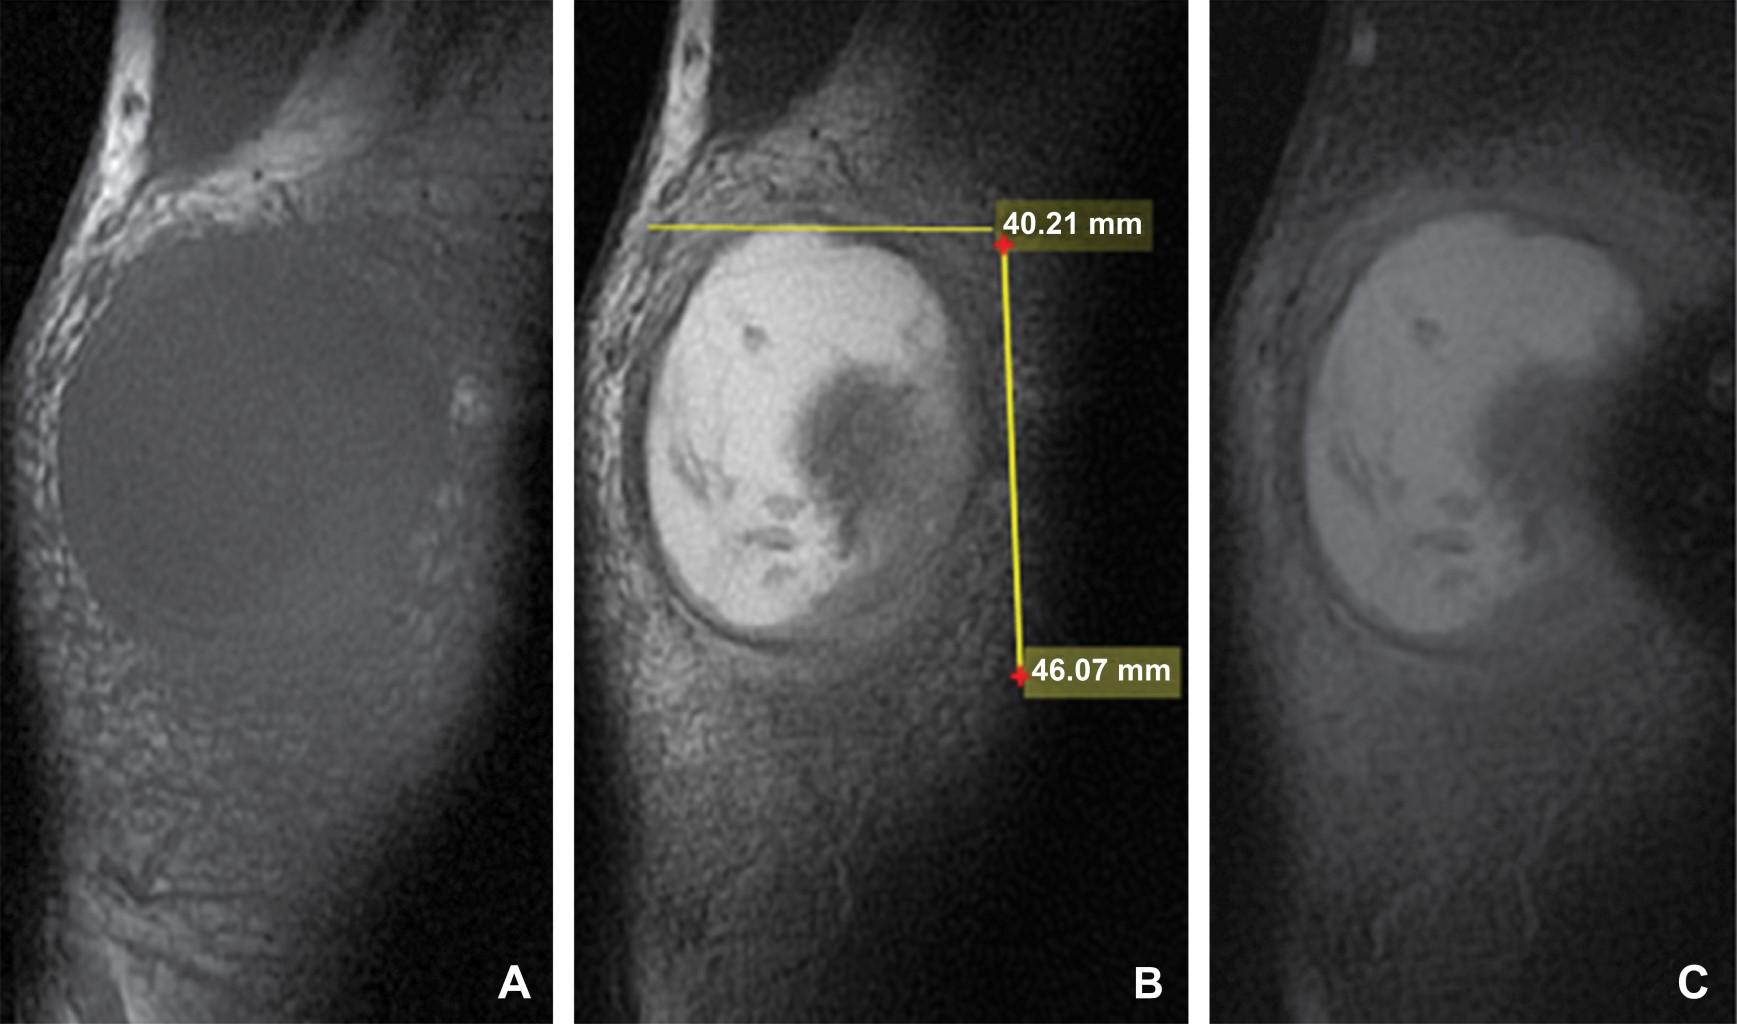

Masculino de 40 años de edad que refiere aparición de zona de enrojecimiento y pequeño abultamiento a nivel del codo izquierdo de tres semanas de evolución, inicialmente adjudicada a piquete de insecto. Acude a médico particular que le administra tratamiento antibiótico sin mejoría, por lo que acude a una segunda evaluación médica donde a la exploración física se evidencia un notable aumento de volumen en región olecraneana, de consistencia blanda con eritema, razón por la que su médico decide investigar a fondo y solicita estudios de laboratorio, los cuales revelaron una elevación de los niveles séricos de ácido úrico y se diagnosticó con gota, por tal motivo se solicita resonancia magnética de codo izquierdo. En el estudio de resonancia magnética simple se identifica una imagen sacular a nivel del olecranon, bien delimitada, heterogénea en su interior, de comportamiento isointenso heterogéneo en el T1, hiperintenso heterogéneo en el T2 e hiperintenso heterogéneo en el T2 con saturación grasa. Dicha imagen midió 39.8 × 14.8 mm en el plano axial, 18 × 46.5 mm en el plano sagital y 40.21 × 46.07 mm en el plano coronal (Figuras 1, 2 y 3), con una pared que midió 2.42 mm de grosor (Figura 2); localizada a nivel de las bursas del olécranon en específico a nivel de la bursa olecraneana superficial.

Figura 3